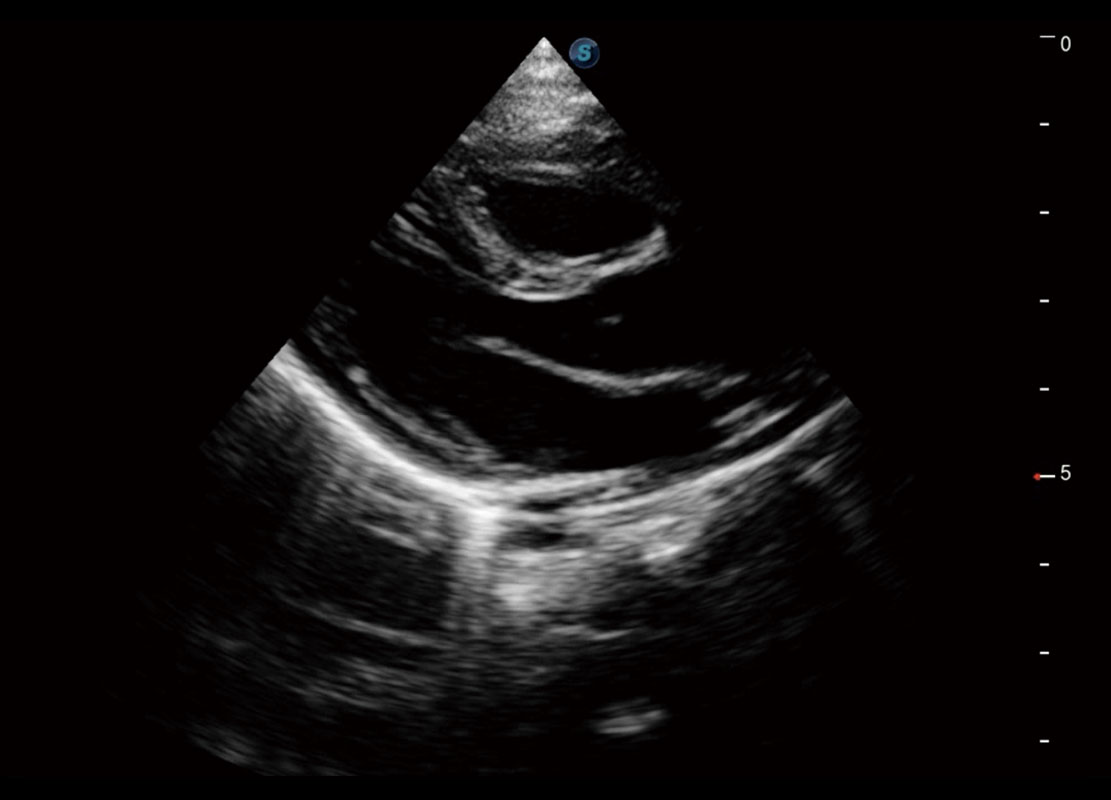

新生儿心脏

P60搭载宽频带线阵探头、宽景成像、弹性成像技术,为您提供乳腺应用方案。P60支持高频相控阵探头、线阵探头、腹部高频探头、腹部微凸探头等,丰富的探头群搭载敏感的彩色血流成像,适用于新生儿多种脏器检测要求,满足新生儿筛查需求。